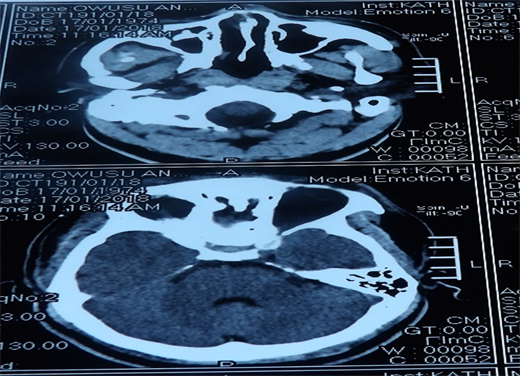

Extended Focused Assessment with Sonography for Trauma (eFAST) was positive for left pleural space collection but negative for haemoperitoneum and haemopericardium. Diagnosis of chest trauma with left Pneumohaemothorax and multiple facial abrasion secondly to road traffic accident was made. So the patient was started with Intravenous fluid with a litre of Ringers lactate run fast, antibiotics, i.v cefuroxime 1.5 g start, and blood was taken for complete blood count, chemistry, kidney and liver function tests. Serum was also group-match against 4 units of blood. Antitetanus prophylaxis, i.m tetanus toxoid, ATS 1500 UI doses given and a size 36 FG chest tube was passed under local infiltration draining immediately 1200 mls of blood and the tube was clamped. Another 700 mls of blood was drained after an hour when the clamp was released, therefore a massive haemothorax diagnosis was made and the patient was then prepared for surgery. Chest x-ray after the chest tube insertion showed a left lower opacification with pleural effusion as shown in Figure 1. As patient being prepared for surgical exploration, he suddenly became totally blind, so an urgent CT head scan was requested and the neurosurgeons and ophthalmology surgical teams consulted. However, he had remained stable after two units of whole blood transfusion. The CT scan of the Head showed basal skull fracture with bilateral occipito-parietal, non-hemorrhagic contusions as shown in Figure 2 and the neurosurgeons recommended a conservative management upon review. However after

Figure 2. Head CT Scan showing basal skull fracture with bilateral occipito-parietal, non-hemorrhagic contusion.